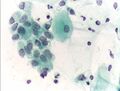

لاختبار عنق الرحم تظهر التغيرات في فيروس الهربس البسيط . صبغة عنق الرحم .